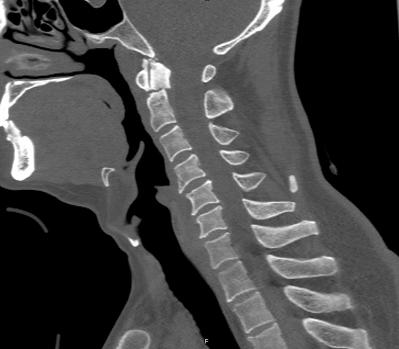

近日,45岁的王先生因高处坠落伤致颈部疼痛、活动受限,于是到北京友谊医院就诊。结合CT结果,医生诊断王先生为枢椎齿状突II型骨折,需手术治疗,王先生被收入骨科病房。

辅助检查显示:颈椎前部可及多发血肿,枢椎齿状突骨折部位向后方移位。

术中,手术团队对王先生颈部重要的策划结构均进行了较好的保护,而且一次性成功的置入空心钉固定骨折断端。手术持续了近5个小时,术后王先生症状明显缓解,无神经损伤。术后复查X线显示齿状突复位,螺钉位置良好。目前王先生已顺利出院,并对北京友谊医院骨科中心的服务进行了高度的评价。

术后显示齿状突复位,螺钉位置良好